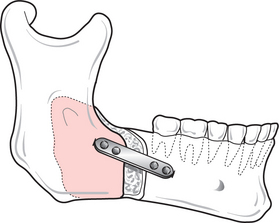

Surgery of the mandible can be applied to any point on the ramus, body or the dentoalveolar segment, although ramus surgery is the most common. The two classical operations—the sagittal split osteotomy (SSO) and the vertical subsigmoid (VSS)—have been adapted and modified in various ways from those originally described.

Sagittal split surgery—where the ramus and posterior part of the mandible are sectioned between the buccal and lingual surfaces—can be used to treat both the severe class 2 and class 3 malocclusion, whereas the VSS is used only to correct relatively mild prognathism. The sagittal split is performed via an intraoral approach (Figs 12.13, 12.14). The lingual tissues are retracted posteriorly and retained using one of the special retractors developed for this purpose. Buccally, the periosteum is retracted to the lower border of the mandible in the second molar region. The lingual bone cut is made horizontally, through the cortical plate, above the level of the lingula; in the past it was extended to the posterior margin of the ramus but this degree of extension is not necessary and may contribute towards relapse. The sagittal cut is made as lateral as is practicable on the external oblique ridge and extended as far forwards as necessary to ensure adequate contact of the split surfaces after repositioning. Finally the buccal cut is made vertically to the lower border. Bone cuts can be undertaken with burs but reciprocating and oscillating saws are more efficient and less likely to cause soft-tissue damage. Once the cuts have been completed the mandible is carefully split using ultra-fine osteotomes. The inferior dental nerve should be identified (usually towards the buccal aspect) during this process and gently dissected away from its canal.

Fig. 12.14 Forward-sliding sagittal split osteotomy. Fixation with miniplates improves stability, and reduces morbidity and the risk of relapse.